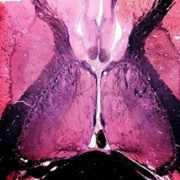

Tracts and Nuclei

Please click one of the following photos to enter the respective section.

Section #1